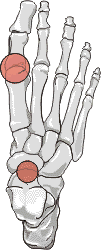

Gout: Erosions bases of metatardal bones

++

+